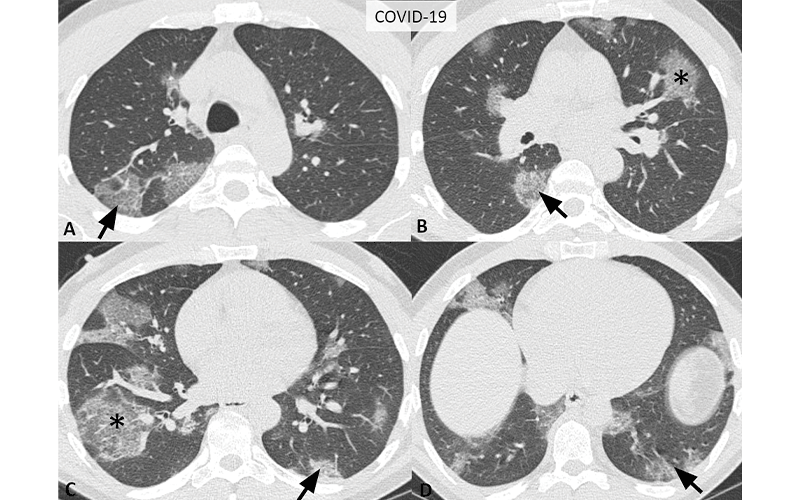

Typical CT imaging features for COVID-19. Unenhanced, thin-section axial images of the lungs in a 52-year-old man with a positive RT-PCR (A-D) show bilateral, multifocal rounded (asterisks) and peripheral GGO (arrows) with superimposed interlobular septal thickening and visible intralobular lines (“crazy-paving”).